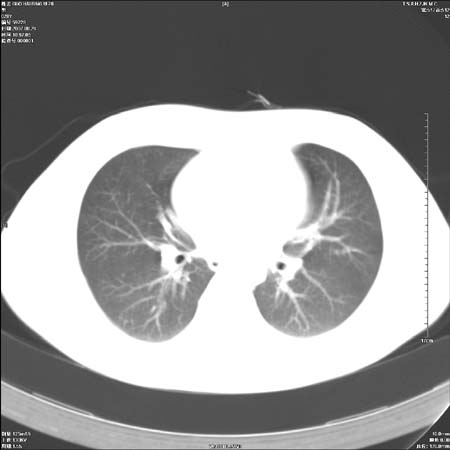

男性,28岁,体检发现左肺病变,患者只有背部隐痛感,哀哉,真不忍心下诊断啊。

左肺门区软组织肿块,左肺上叶支气管开口消失,纵隔内见肿大淋巴结,考虑左中心型肺部,可以做纤支镜取病理确认.

左肺肺门区肿块影,分叶明显:诊断肺癌应该没有疑问。

我觉得定位中央型还是周围型这个有点难。

首先这个病例应该加薄层面扫描-可以很好显示支气管与肿块的情况。

本例倾向周围型肺癌

鉴别:中央型肺癌-肿块那么明显一般合并节段肺不张或阻塞性炎症。

本例肿块边缘外侧可见左上叶各段支气管。

肺癌可能性大。(有分叶,毛刺)

左肺肺门区肿块影,分叶明显,左肺上叶支气管开口受压,纵隔内见肿大淋巴结,考虑左中心型肺癌。

左侧肺门区见一块状病灶可见分叶,纵隔内及左肺门见肿大淋巴结,应该是周围型肺癌而不是中心型肺癌,原因有以下2点,1未见阻塞肺气肿和阻塞性炎症,这么大肿块如果是中心型肺癌就是未分化型或小细胞型肺癌不出现阻塞性肺不张也应该有阻塞炎症或阻塞性肺气肿,2如果是中心型肺癌临床出现最早的症状是咳嗽(此时可无任何异常影象),而此人这么大肿块只有背部隐痛是体检才发现无法解释.

左肺门区分叶状软组织肿块,纵隔内有肿大淋巴结,诊断肺癌应该问题不大。

直接下肺癌诊断还太早,病灶较大,估计5cm以上,但阻塞性改变及对临近纵隔及支气管侵犯不明显,密度较均匀,弓旁见一单个淋巴结,需要排除炎症性肿块及腺瘤,平滑肌瘤等。